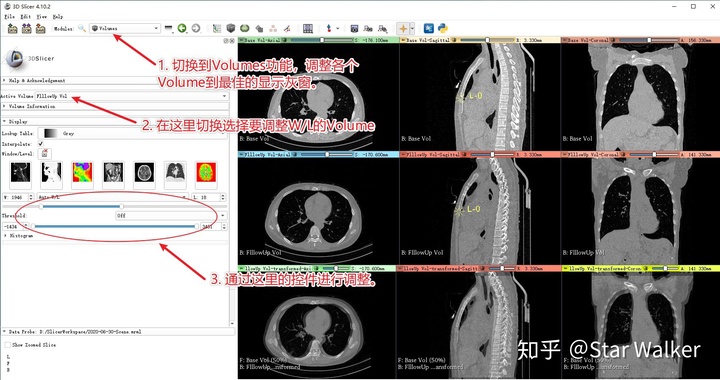

接下来就逐个添加标志点,来对齐脊椎。但在添加标志点之前,可以根据需要,调整图像显示的灰窗设置,调整到一个最有利于观察感兴趣器官或区域的灰窗。选对灰窗,可以让后续的“肉眼找点”操作更快更准哦。操作见下图。